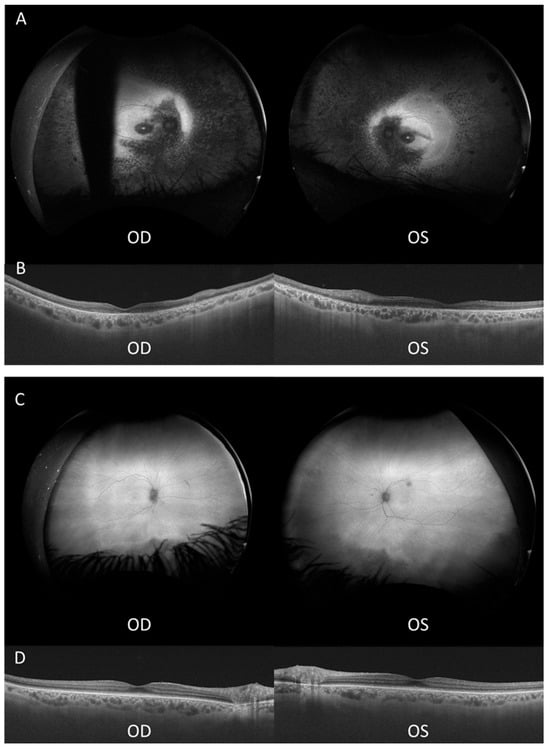

3.1. Clinical Findings